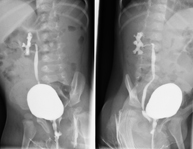

La urografia intravenosa (UIV) consisteix en l'obtenció d'imatges radiològiques seriades del ronyó, vies urinàries i bufeta. Aquest estudi requereix sempre l'ús d'un contrast iodat. - Cistografía (CUMS)

La cistouerotrografia miccional seriada consisteix en l'obtenció d'imatges radiològiques per valorar l'anatomia i la funció de la uretra i la bufeta amb l'administració de contrast iodat a través d'una sonda vesical. - Uretrocistografia (Uretro-Cums)

La uretrocistrografia retrògrada i miccional consisteix en l'obtenció d'imatges radiològiques per valorar l'anatomia i la funció de la bufeta i de la uretra. S'aplica material de contrast a través d'una petita sonda que es troba a la uretra i s'obtenen imatges durant l'ompliment i el buidatge de la bufeta. - Pielografia ascendent per catèter